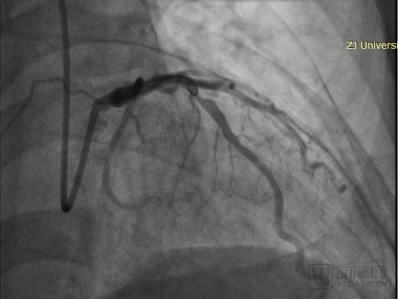

手术过程中,王建安院士团队先使用3.0×13mm规格的棘突球囊预扩张病变血管。随后使用3.5×15mm的矩正冠状动脉血管重塑导管以10atm扩张血管,并启动激光治疗。术后造影显示扩张效果良好,无残余狭窄无夹层,TIMI血流3级,手术圆满完成。

导丝穿过患者病变部位